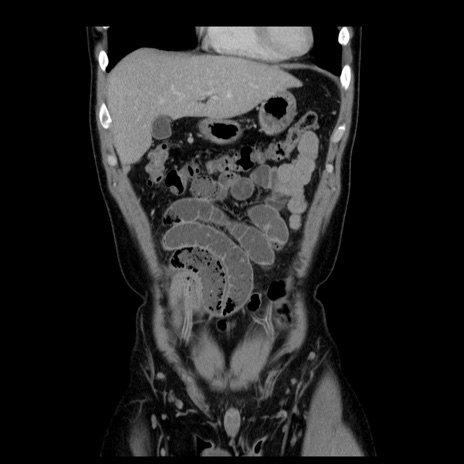

症例4(冠状断像)

【症例】30歳代男性

【主訴】腹痛、嘔吐

【現病歴】昨晩から突然の腹痛あり、その後嘔吐、軟便も出現。腹痛が改善しないため救急搬送となる。2日前にしめ鯖の食事歴あり。

【身体所見】意識清明、苦悶様、BP 135/90mmHg、BT 35.7℃、腹部:平坦、やや硬、心窩部〜臍部に自発痛、圧痛あり、筋性防御+、反跳痛-

【データ】WBC 8100、CRP 0.57